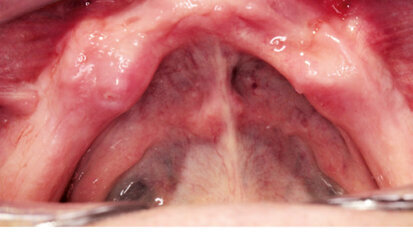

Nový úsměv za jeden den

Čt. 28. května 2020